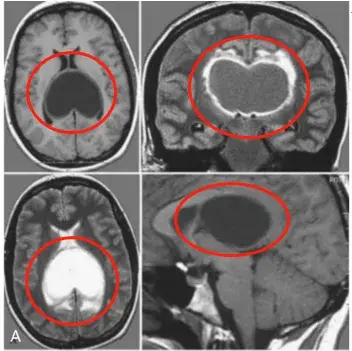

怀孕查出胶质瘤怎么办?可以做CT或者MRI吗?、生下来的孩子会健康吗33岁的凯莉在怀孕期间因严重头痛,走路不稳,记忆力减退等症状就医,MRI图像显示在她的两个侧脑室后部有一个巨大的囊...